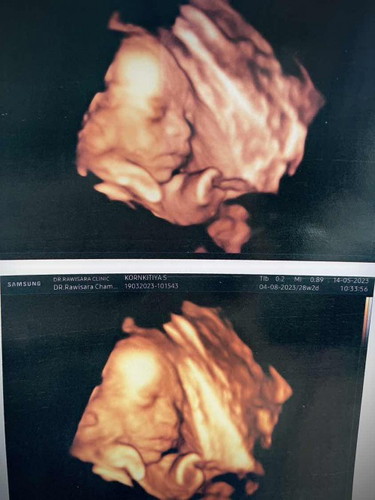

ซาวด์28 w 4 มิติ

น้องให้เห็นแค่ด้านข้าง ถ้าคลอดมาจมูกจะตามภาพมั้ยคะ แม่ไม่แน่ใจว่าโด่งมั้ย 🥹🙏🏻#ท้องแรกคะ

บ้านนี้ก็หันข้างตลอดเลยค่ะ อันนี้ตอน 30 วีค 🤣